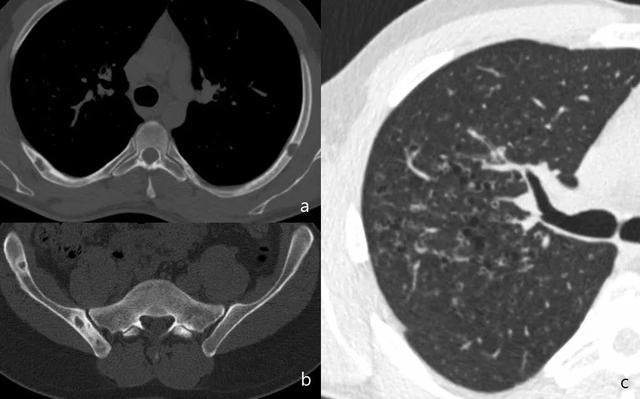

当骨矿化损失超过30%时,在简单的放射线图像中可以发现病变。转移和原发性骨肿瘤不同的一个特征性发现是,转移通常不显示骨膜反应。CT不用于检测,但在评估皮质破坏和评估病理性骨折的风险中起作用(图6)。

图6.转移。在乳腺癌伴肺转移的患者中,多个溶解性病变(a和b)影响胸骨和多个椎体,涉及椎体的后部区域(箭头)。